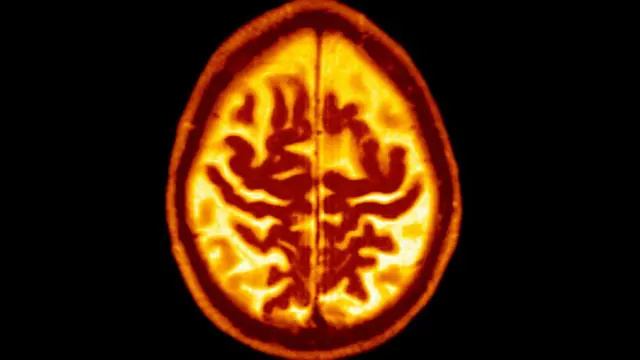

ਕਾਗਨੇਟਿਵ ਟੈਸਟਿੰਗ ਵਿੱਚ ਬਹੁਤ ਸਾਰੇ ਵੱਖ-ਵੱਖ ਟੈਸਟ ਅਤੇ ਨਰੀਖਣ ਸ਼ਾਮਲ ਹੁੰਦੀਆਂ ਹਨ ਜੋ ਇਹ ਮਾਪਦੇ ਹਨ ਕਿ ਮਨੁੱਖੀ ਦਿਮਾਗ ਕਿੰਨੀ ਚੰਗੀ ਤਰ੍ਹਾਂ ਕੰਮ ਕਰ ਰਿਹਾ ਹੈ।

ਇਹ ਟੈਸਟ ਜਿਨ੍ਹਾਂ ਲੋਕਾਂ ਵਿੱਚ ਬੋਧਿਕ ਕੰਮ ਕਾਜ ਦੀ ਯੋਗਤਾ ਘਟੀ ਹੋਵੇ ਦਾ ਪਤਾ ਲਾਉਣ ਦਾ ਸਭ ਤੋਂ ਤੇਜ਼ ਤਰੀਕਾ ਹੈ।

ਮੁਲਾਂਕਣ ਟੈਸਟਾਂ ਵਿੱਚ, ਯਾਦਦਾਸ਼ਤ, ਧਿਆਨ, ਵਸਤੂਆਂ ਨੂੰ ਨਾਮ ਦੇਣ ਦੀ ਯੋਗਤਾ ਦੇ ਨਾਲ-ਨਾਲ ਮੌਖਿਕ ਅਤੇ ਲਿਖਤੀ ਹੁਕਮਾਂ ਦੀ ਪਾਲਣਾ ਕਰਨ ਦੀ ਯੋਗਤਾ ਦੀ ਜਾਂਚ ਕੀਤੀ ਜਾਂਦੀ ਹੈ।

ਕਾਗਨੇਟਿਵ ਟੈਸਟ ਵਿੱਚ, ਡਾਕਟਰ ਮਰੀਜ਼ਾਂ ਨੂੰ ਨਵਾਂ ਕੁਝ ਸਿੱਖਣ ਅਤੇ ਯਾਦਦਾਸ਼ਤ ਨਾਲ ਸਬੰਧਤ ਕਈ ਤਰ੍ਹਾਂ ਦੇ ਸਵਾਲ ਪੁੱਛਦੇ ਹਨ।

ਪਰ ਇੱਕ ਲੰਬੇ ਸਮੇਂ ਦੇ ਕਲੀਨਿਕਲ ਮੁਲਾਂਕਣ ਵਿੱਚ ਕਾਗਨੇਟਿਵ ਟੈਸਟਾਂ ਦੇ ਨਾਲ-ਨਾਲ ਸਰੀਰਕ ਅਤੇ ਨਿਊਰੋਲੌਜੀਕਲ ਟੈਸਟ ਅਤੇ ਮਰੀਜ਼ ਦਾ ਪੂਰਾ ਪਿਛੋਕੜ ਜਾਣਨਾ ਸ਼ਾਮਲ ਹੁੰਦਾ ਹੈ।